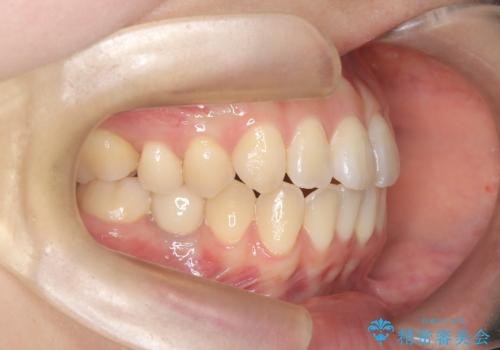

- 患者様は、右下第2小臼歯(5番)の先天欠如により乳歯が残存している状態でした。

加えて、**下顎前歯部に叢生(歯のがたつき)**が見られ、審美的・機能的な改善を希望されて来院されました。

診査の結果、乳歯は長期間機能していましたが、将来的な脱落のリスクが高く、インプラントによる永久歯の補綴が望ましいと判断しました。

また、欠損部にインプラントを埋入するには、前後の歯の傾斜改善とスペース確保のための矯正治療が必要でした。

下顎前歯の叢生も同時に改善できるよう、全体的なワイヤー矯正による治療計画を立案しました。